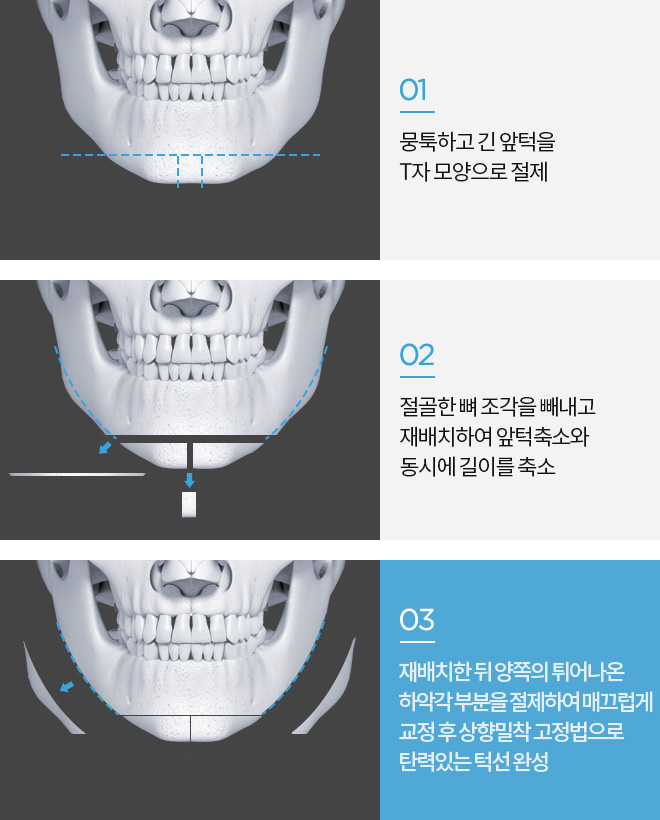

앞턱 절골 수술방법

T 절골법

처짐은 예방하고 매끈한 턱선

근막층을 상향밀착고정하기에 이중턱이 되는 원인을 차단하여 처짐 예방과 매끈한 턱선 완성